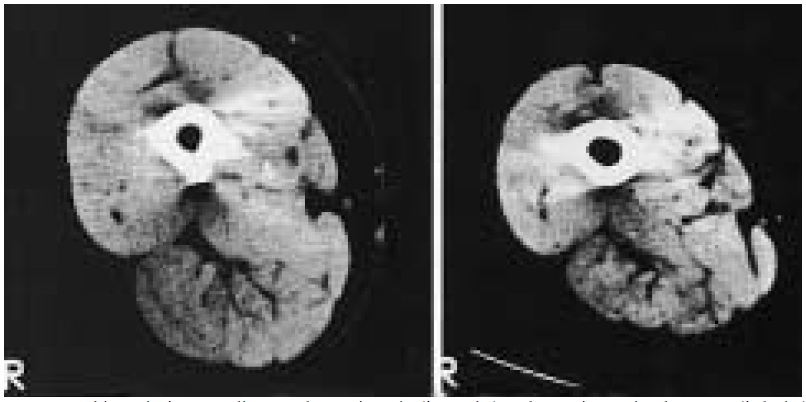

Figure.2 : Tomographie assistée par ordinateur d’un sujet sain (à gauche) et d’un sujet atteint de BPCO (à droite) appartenant au même groupe d’âge. [20]

Un dysfonctionnement musculaire squelettique chez les sujets atteints de BPCO est nettement mis en valeur lors d’études comparatives face à des personnes saines [4]. Ce dysfonctionnement se traduit par une faiblesse musculaire prononcée de manière plus importante au niveau des membres inférieurs que des membres supérieurs [13]. Les enregistrements faits au niveau sanguin et pulmonaires lors de tests de marches de 6 minutes (TM6) mettent en évidence une inflammation et un stress oxydatif associés à cette perte de masse musculaire [14,15]. Il est aussi rapporté chez ces patients une importante réduction des fibres de type I couplée à la réduction des enzymes oxydatives et glycolytiques au niveau des membres inférieurs [16]. Il est remarqué par la même occasion, une acidose lactique plus précoce due à l’inactivité et au déconditionnement musculaire [17]. Cette atrophie musculaire est associée à une augmentation de la proportion des fibres de type II et plus précisément des IIb. Les auteurs [4,13,15-17] suggèrent que la forte proportion des fibres II est en relation avec l’hypoxémie et à plus long terme avec l’inactivité, entraînant une baisse de la dépense énergétique journalière [18].

Même si le poids corporel global ne change pas, la masse musculaire quant à elle, subit une diminution importante. Pour donner un exemple, la force du quadriceps diminue d’environ 30% [19]